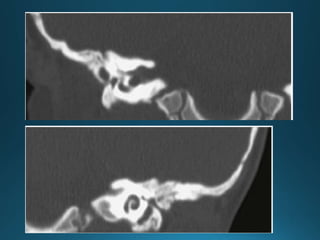

11.

External auditory canal atresia (EACA) is characterised by complete or incomplete

bony atresia of the external auditory canal (EAC)

Findings in the middle ear are variable and the inner ear and inner auditory canal are

typically normal

number of syndromes are associated with external auditory canal atresia 2.These

include:

• Crouzon syndrome

• Treacher Collins syndrome

• Goldenhar syndrome

• Pierre Robin syndrome

External auditory canalatresia (EACA) is characterised by complete or incomplete bony atresia of the external auditory canal (EAC) Findings in the middle ear are variable and the inner ear and inner auditory canal are typically normal number of syndromes are associated with external auditory canal atresia 2.These include: • Crouzon syndrome • Treacher Collins syndrome • Goldenhar syndrome • Pierre Robin syndrome